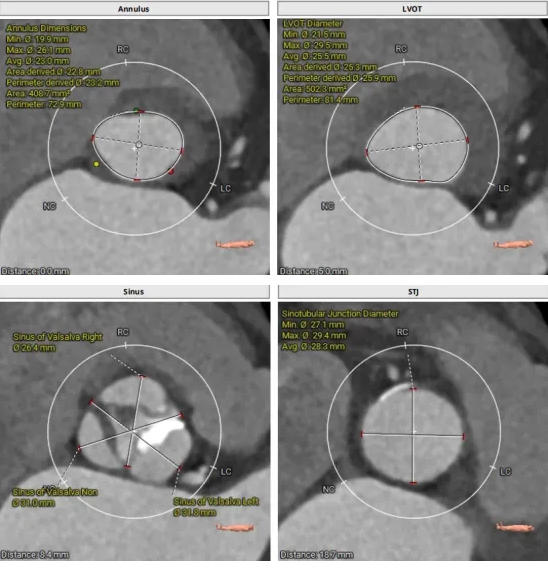

CT結(jié)構(gòu)評(píng)估

患者為功能性二葉瓣,瓣葉增厚,輕度鈣化,鈣化主要集中在左竇瓣葉上,左冠脈高度較低,結(jié)合瓣葉長度,竇部結(jié)構(gòu)綜合評(píng)估左冠風(fēng)險(xiǎn)較低,但左冠瓣葉瓣尖處有鈣化團(tuán)塊,在球擴(kuò)以及瓣膜釋放時(shí)仍需注意左冠灌注情況,由于鈣化團(tuán)塊位置特殊,建議做冠脈保護(hù)處理,右側(cè)股動(dòng)脈作為主入路,穿刺點(diǎn)位于股骨頭中段即可。

采取局麻+鎮(zhèn)靜麻醉方式,避免氣管插管對(duì)循環(huán)打擊;預(yù)裝VenusA L26瓣膜,患者心功能較差不進(jìn)行球囊預(yù)擴(kuò)張,直接放瓣膜;升主動(dòng)脈稍寬,注意器械通過,必要時(shí)snare輔助;建議行左冠保護(hù);右股動(dòng)脈作為主入路。